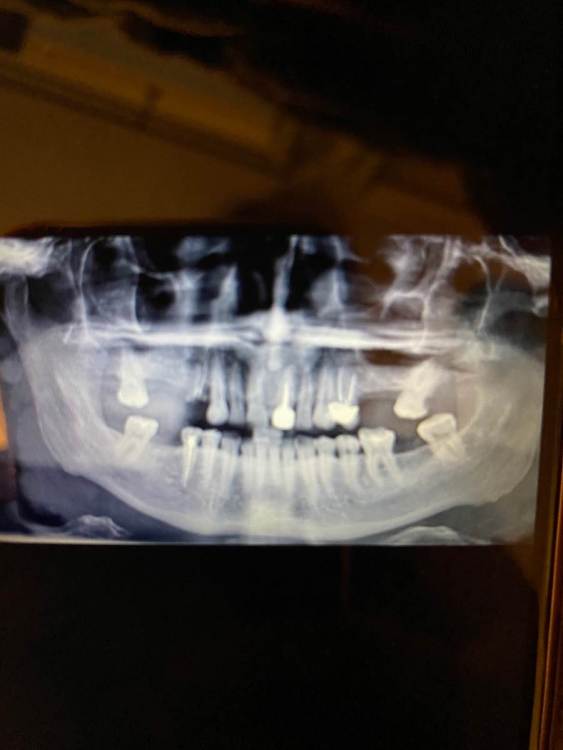

Bonya Опубликовано 26 мая, 2023 Поделиться Опубликовано 26 мая, 2023 Посоветуйте пожалуйста опытного хирурга имплантолога в Москве. Нужно установить импланты . нужен синус лифтинг? Какие импланты лучше поставить? Ссылка на комментарий